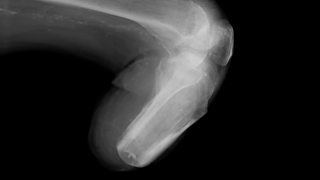

Duncan's leg was amputated 18 yrs ago, but he still endures "phantom pain".